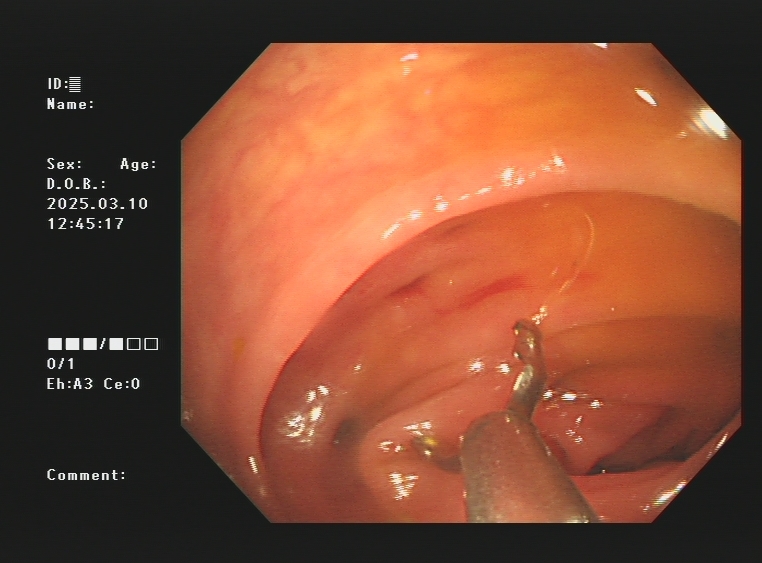

1.上消化道出血常见原因:消化性溃疡(胃溃疡、十二指肠溃疡)、食管炎、急性糜烂出血性胃炎、上消化道肿瘤(食管癌、胃癌)、剧烈呕吐造成的食管贲门黏膜撕裂伤、肝硬化引起的食管胃底静脉曲张。以下是一些常见的上消化道出血内镜图片:

急性胃黏膜病变出血、十二指肠球部溃疡出血及镜下止血夹止血

肝硬化引起的食管及胃底重度静脉曲张镜下止血

食管贲门黏膜撕裂出血